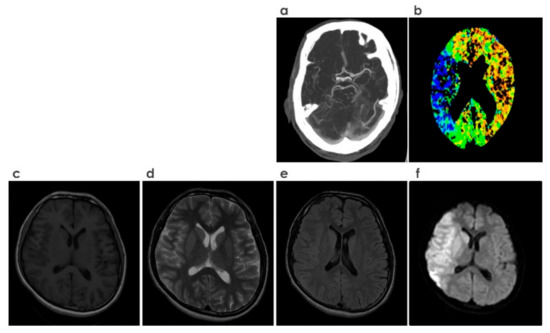

| MRI | MRI is based on the magnetization properties of atomic nuclei. Protons in the water nuclei of tissues are excited and relaxed, and subsequently capturing the released energy. Based on the relaxation time, T1 and T2 tissues are characterized [32]. |

| T1 weighted (MRI) | Characterized by shorter relaxation time. Following noticeable changes in scans [32]

|

| T2 weighted (MRI) | Characterized by longer relaxation time. Following noticeable changes in scans [32]

| Flair (MRI) | Characterized by longer relaxation time than T2 weighted images. Following noticeable changes in scans [32]

| DWI (MRI) | Detect the random movements of water protons. Spontaneous movements, rapidly become restricted in ischemic brain tissue which appear bright in scans. It is an extremely sensitive method for detecting acute stroke. [32] Apparent diffusion coefficient (ADC) is a measure of the magnitude of diffusion (of water molecules) within tissue. Rough values (10−6 mm2/s):